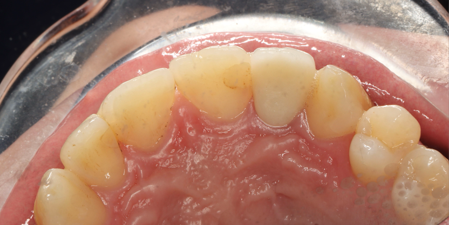

1/6/2025,post placement,tooth preparation,impression taking

1/16/2025: All-ceramic crown restoration for #12; patient asymptomatic